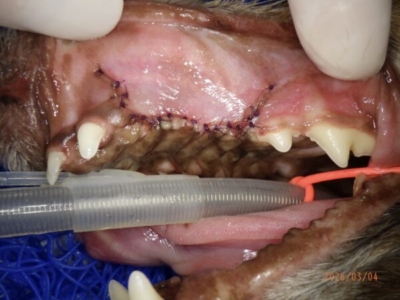

細かく吸収糸で縫合

右上顎も同様に。歯肉の下がっていた第二前臼歯まで抜歯。

内側は想像以上に骨がなくなっていた

被せるための歯肉を丁寧に調整していく

引き攣らないように緻密に縫合していく